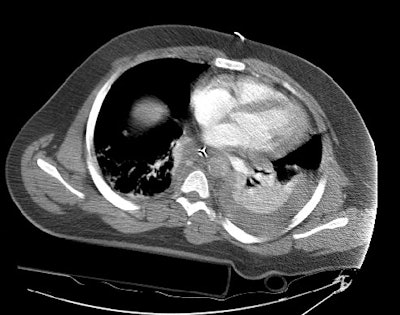

Images through the abdomen revealed a severely diminished aortic caliber and poor organ perfusion consistent with hypovolemic shock. The patient expired prior to angiography.